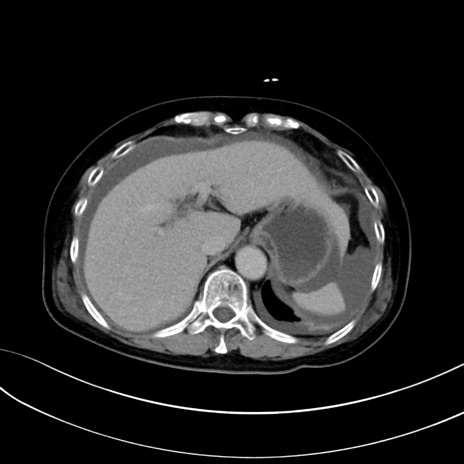

症例13 CT(横断像)1日半後